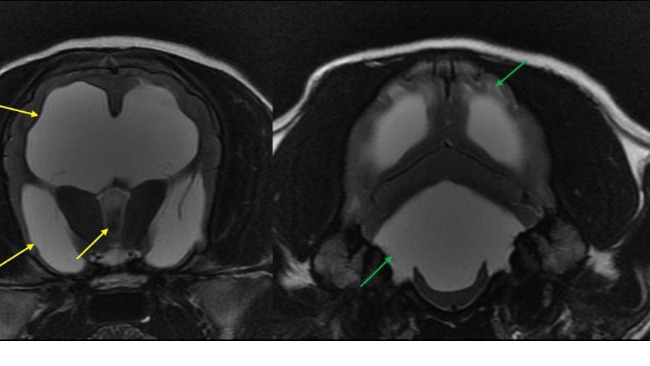

Po wizycie u neurochirurga i wykonaniu rezonansu stan szczeniaka spowodowany jest nagromadzeniem się płynu w czaszce, który uciska na nerwy powodując ból. Prościej choruje na wodogłowie.

Wstawiam Wam zdjęcia z prześwietlenia i opis.

Ten biały obszar który widać na zdjęciu to płyn, a czarny to mózg który jest uciskany.